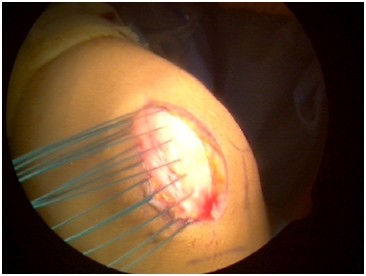

Diagnostic arthroscopy is used to define all intra-articular pathology. Soft tissue injuries including partial meniscal tears, synovitis and chondromalacia are addressed first, followed by osteochondral defects along the patella and/or lateral femoral condyle. Depending on the extent of the chondral injury and the quality and size of the detached fragment (Figure 1), either internal fixation of the fragment or a microdrilling technique is employed. If internal fixation was employed, often the pathology was addressed after the arthroscopic procedure was completed. The medial border of the patella is evaluated arthroscopically. Finally, a medial parapatellar incision measuring 3 to 4 cm is made. Dissection is carried through the skin, subcutaneous tissue and musculo-ligamentous structures until the MPFL remnant is identified. The ligament is assessed at both the patellar and femoral insertions. In the cases reviewed here, the remnant was large enough to be repaired using six to eight 2-0 poly (ethylene, terephthalate) sutures, using a pants-over-vest technique with the knee in 30° of flexion (Figure 2). The tears were found to be midsubstance and not avulsed from either the patella or femoral insertion. A varus stress is then applied to the patella to confirm adequate tensioning of the repair before the knee is taken through the full range of motion to assess patellar tracking. A standard closure of the subcutaneous tissues (Figure 3) is performed with 2-0 Vicryl (polyglactin 910; Ethicon, Somerville, NJ) before the skin is closed with a running Monocryl stitch (poliglecaprone 25; Ethicon). At the conclusion of the surgery, the knee is placed in an immobilizer, which the patient must wear until the first postoperative visit.

Figure 1 Arthroscopic visualization of patellar injury.